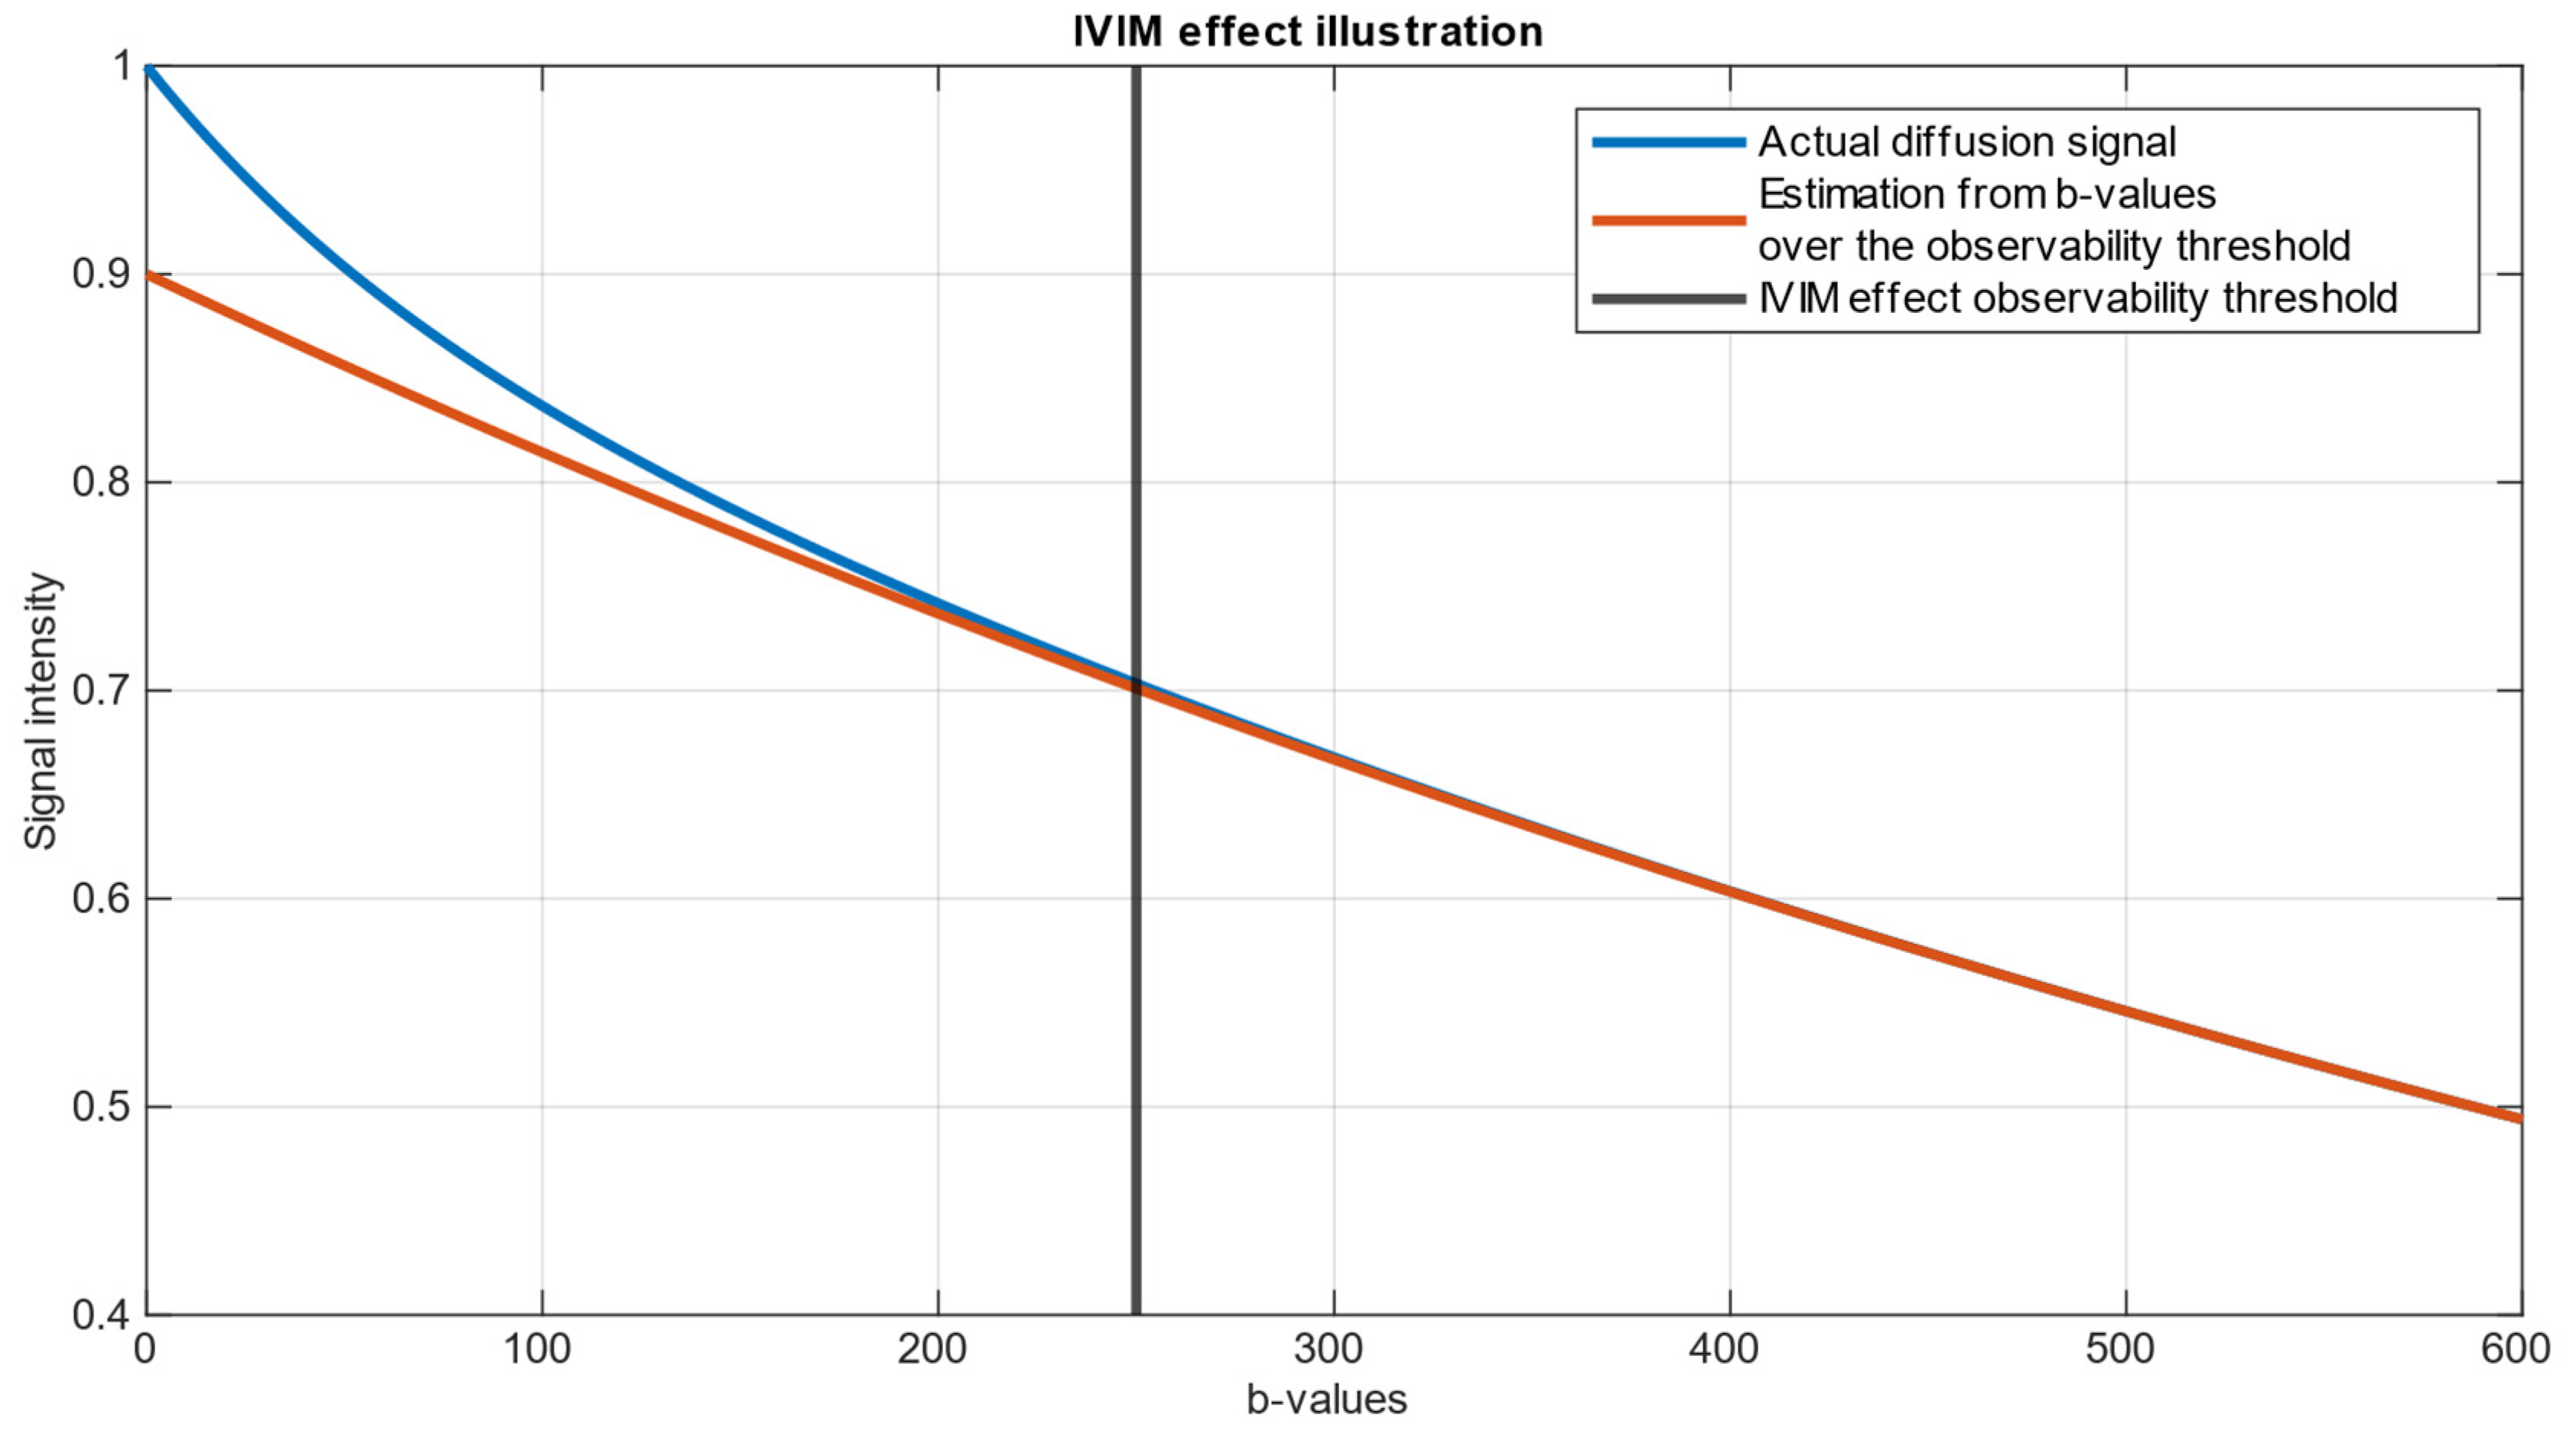

1. Introduction

- represents the measured signal intensity in the DWI image for a given .

- stands for b-value—diffusion weighting factor, determined by the strength and timing of the diffusion gradients prior to signal echo.

- is the signal intensity in the absence of diffusion weighting ().

- represents the fraction of signal coming from quick-diffusing water molecules, which are assumed to be circulating in the blood, also referred to as the perfusion fraction.

- is the pseudo-diffusion coefficient, which reflects the diffusion of water in capillaries and small vessels.

- represents the true diffusion coefficient, which characterizes the diffusion of extravascular water molecules.